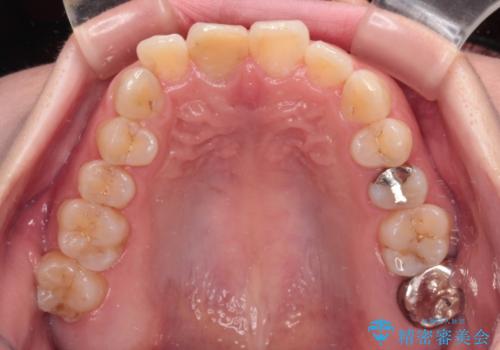

- 事故でぶつけて神経を取り除いた歯が変色したとのことで来院された患者様です。

処置直後は欠けた部分を詰めた材料で見た目に問題なかったそうですが、年々変色してきて、かなり目立つようになっていました。

根管治療された状態に大きな問題はなかったため、土台を植立し、オールセラミッククラウンにて補綴治療を行うこととしました。